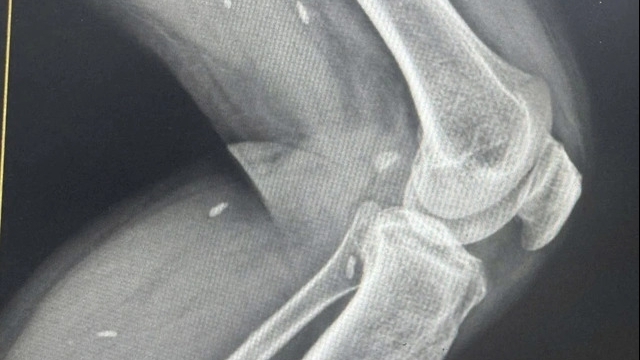

![]() |

| Bác sĩ CKII Nguyễn Hoàng Phương - Phó Giám đốc phụ trách Trung tâm Y tế huyện Yên Lạc hướng dẫn bệnh nhân chụp X quang. |